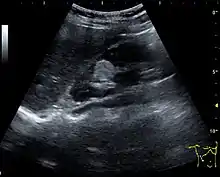

Renal ultrasonography of a person with tuberous sclerosis and multiple angiomyolipomas in the kidney: Measurement of kidney length on the US image is illustrated by '+' and a dashed line.